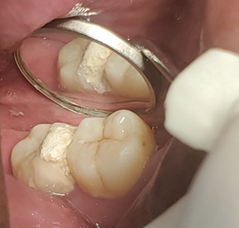

Al interrogatorio paciente refirió antecedente de tratamiento de operatorio en la pieza 4,8 iniciado hace 2 meses atrás y que posterior a un 1 mes se fracturó; el borde afilado de la cúspide mesiolingual tenía la apariencia de una punta de lanza que traumatizaba la lengua (Figura 2). Inicialmente señaló que la cúspide fracturada provocó fricción en la lengua y después de 3 semanas apareció una pequeña úlcera que fue creciendo hasta el tamaño actual.

Para planificar la conducta terapéutica de la pieza 4,8 se solicitó una radiografía periapical, que evidenció la dilaceración de las raíces y la calcificación de los conductos radiculares; a nivel periapical se observó un área radiolúcida (Figura 3). Por lo que se sugirió como una opción terapéutica la exodoncia de la pieza 4.8.